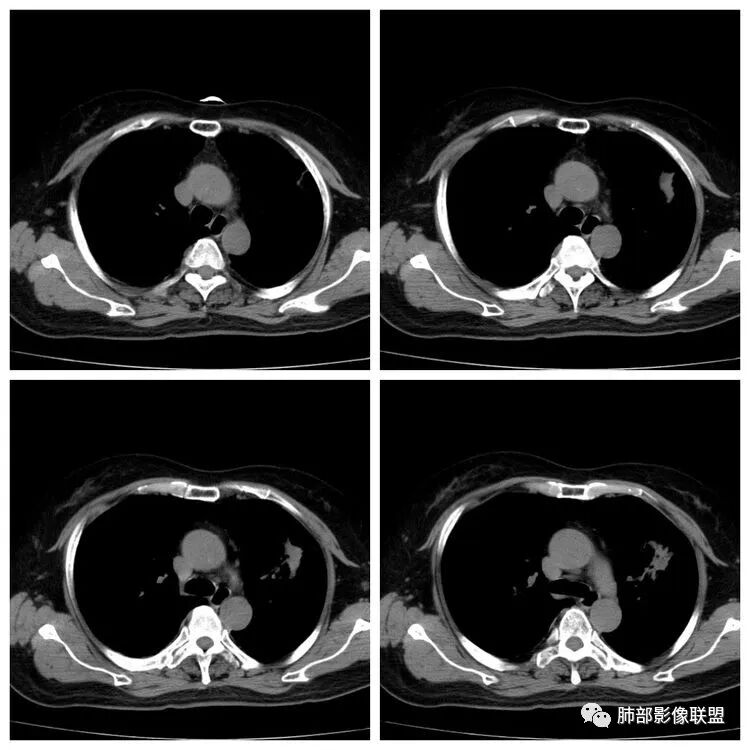

以下是两个时间点左右对比

2019.11.26  👇                           2020.01.20👇                                            2019.11.26片

2020.01.20片

2.早期CT表现左肺上叶不规则团块影,呈混合密度,以实性密度为主,但整体密度偏低,周围隐约见磨玻璃密度影。

边缘不规则,前内侧缘见小叶间隔限制(注意,并非典型深分叶),病灶外侧细长毛刺,病灶内有小空泡及空气支气管征,有胸膜牵拉征象。

上述征象均提示病灶为恶性病灶,但边缘特征及空气支气管征似乎有别于常见的浸润性腺癌及MALT。

可惜没有增强扫描提供更多信息。

3.复查影像显示病灶整体大小变化不明显,其内空泡消失,但是周围磨玻璃影趋于似清非清,整体病灶收缩力中等偏弱,均提示粘液腺癌的可能性大。